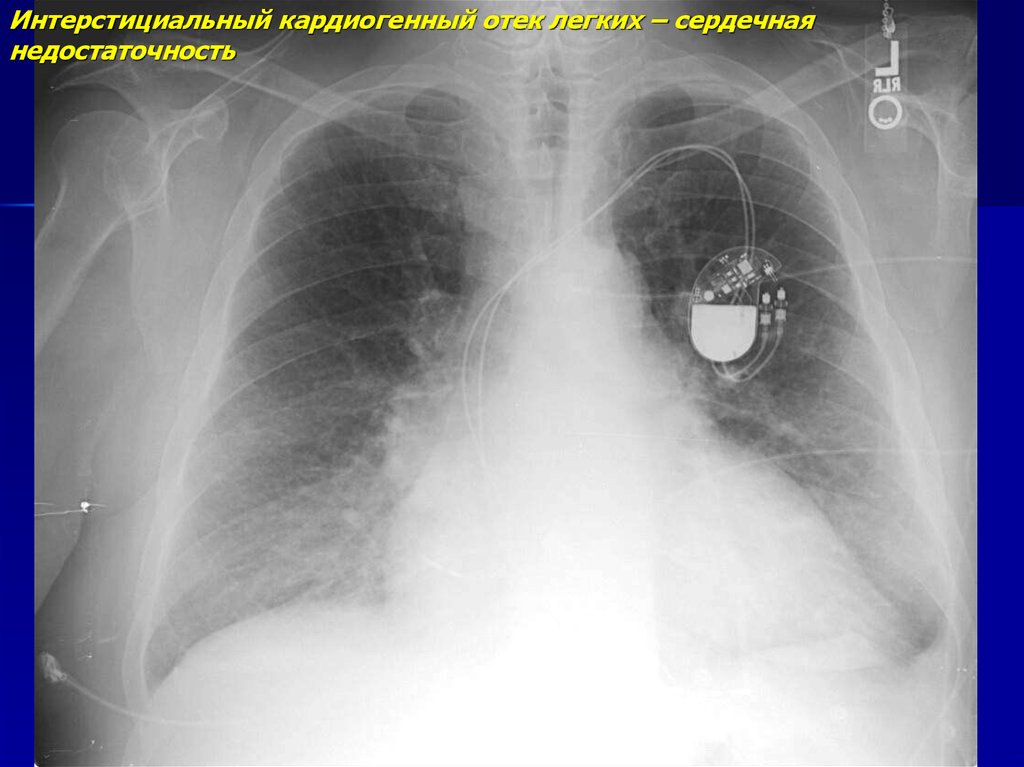

Симптомы и причины скопления воды в легких